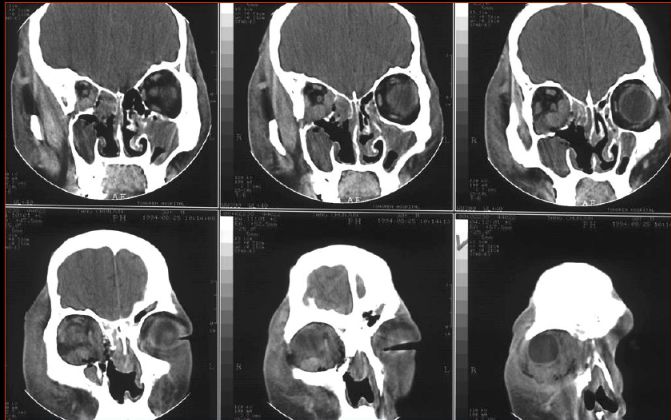

影像学检查

鼻窦炎发病2周内,在影像学检查上表现不明显,因此急性鼻-鼻窦炎发病2周内如无怀疑其他疾病,可直接治疗,观察病情发展,不需影像学检查。

X线片检查不能准确定位鼻腔和鼻窦内病变的部位,尤其是比较重要而且精细的结构,如鼻道窦口复合体等部位,而且图像不够清晰,容易造成误诊,因此,临床已少用。

目前多使用鼻窦CT来了解鼻腔及鼻窦的病变,明确是否存在粘膜炎症或骨结构异常等。使用CT对鼻窦炎病情严重程度进行分型(Lund-Mackey分级)在临床上已经作为一种基本的评估方法进行使用,主要用于了解具有临床症状的慢性鼻窦炎患者的病情。

但临床上经CT检查发现约60%的正常儿童存在鼻腔或鼻窦粘膜水肿的表现,因此,CT不能用作诊断慢性鼻窦炎的金标准,应结合病史、临床表现、专科查体和必要的辅助检查共同确定诊断。